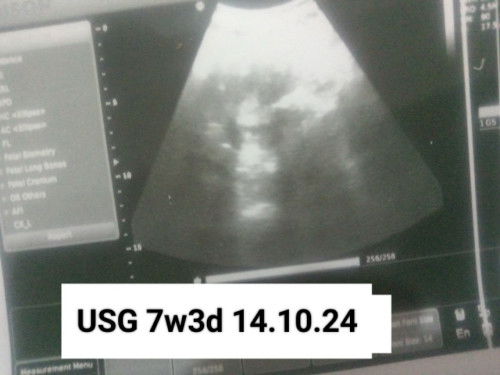

Kemarin tanggal 14-10-24 saya keguguran. Dan sampai sekarang ini 08-01-25 gak pernah ada lagi haid. Iseng tespect karna saya alami kembali itu gejala kehamilan. Kaya mual. Sering BAK. Patudara nyeri. Dan ternyata 4kali tespect garis 2 bun tesnya . Dan PERTANYAANYA!! " APAKAH BISA HAMIL TANPA ADA MENSTRUASI TERLEBIH DULU???"#Sharingdong_Bund #bantujawab #mohonbantujawabbunda #sharing #Tanya